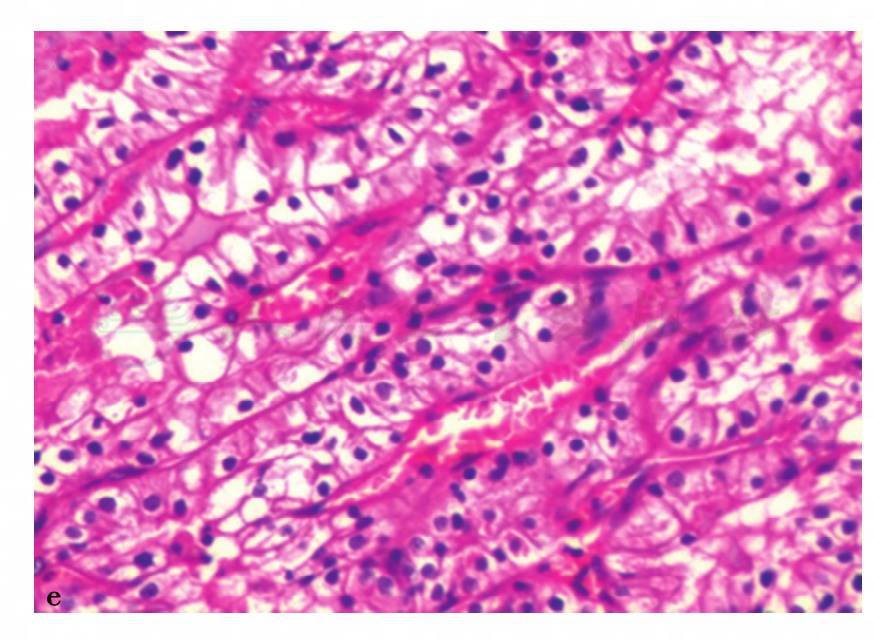

图13 e,病理诊断:右肾透明细胞癌FurhmanⅡ级